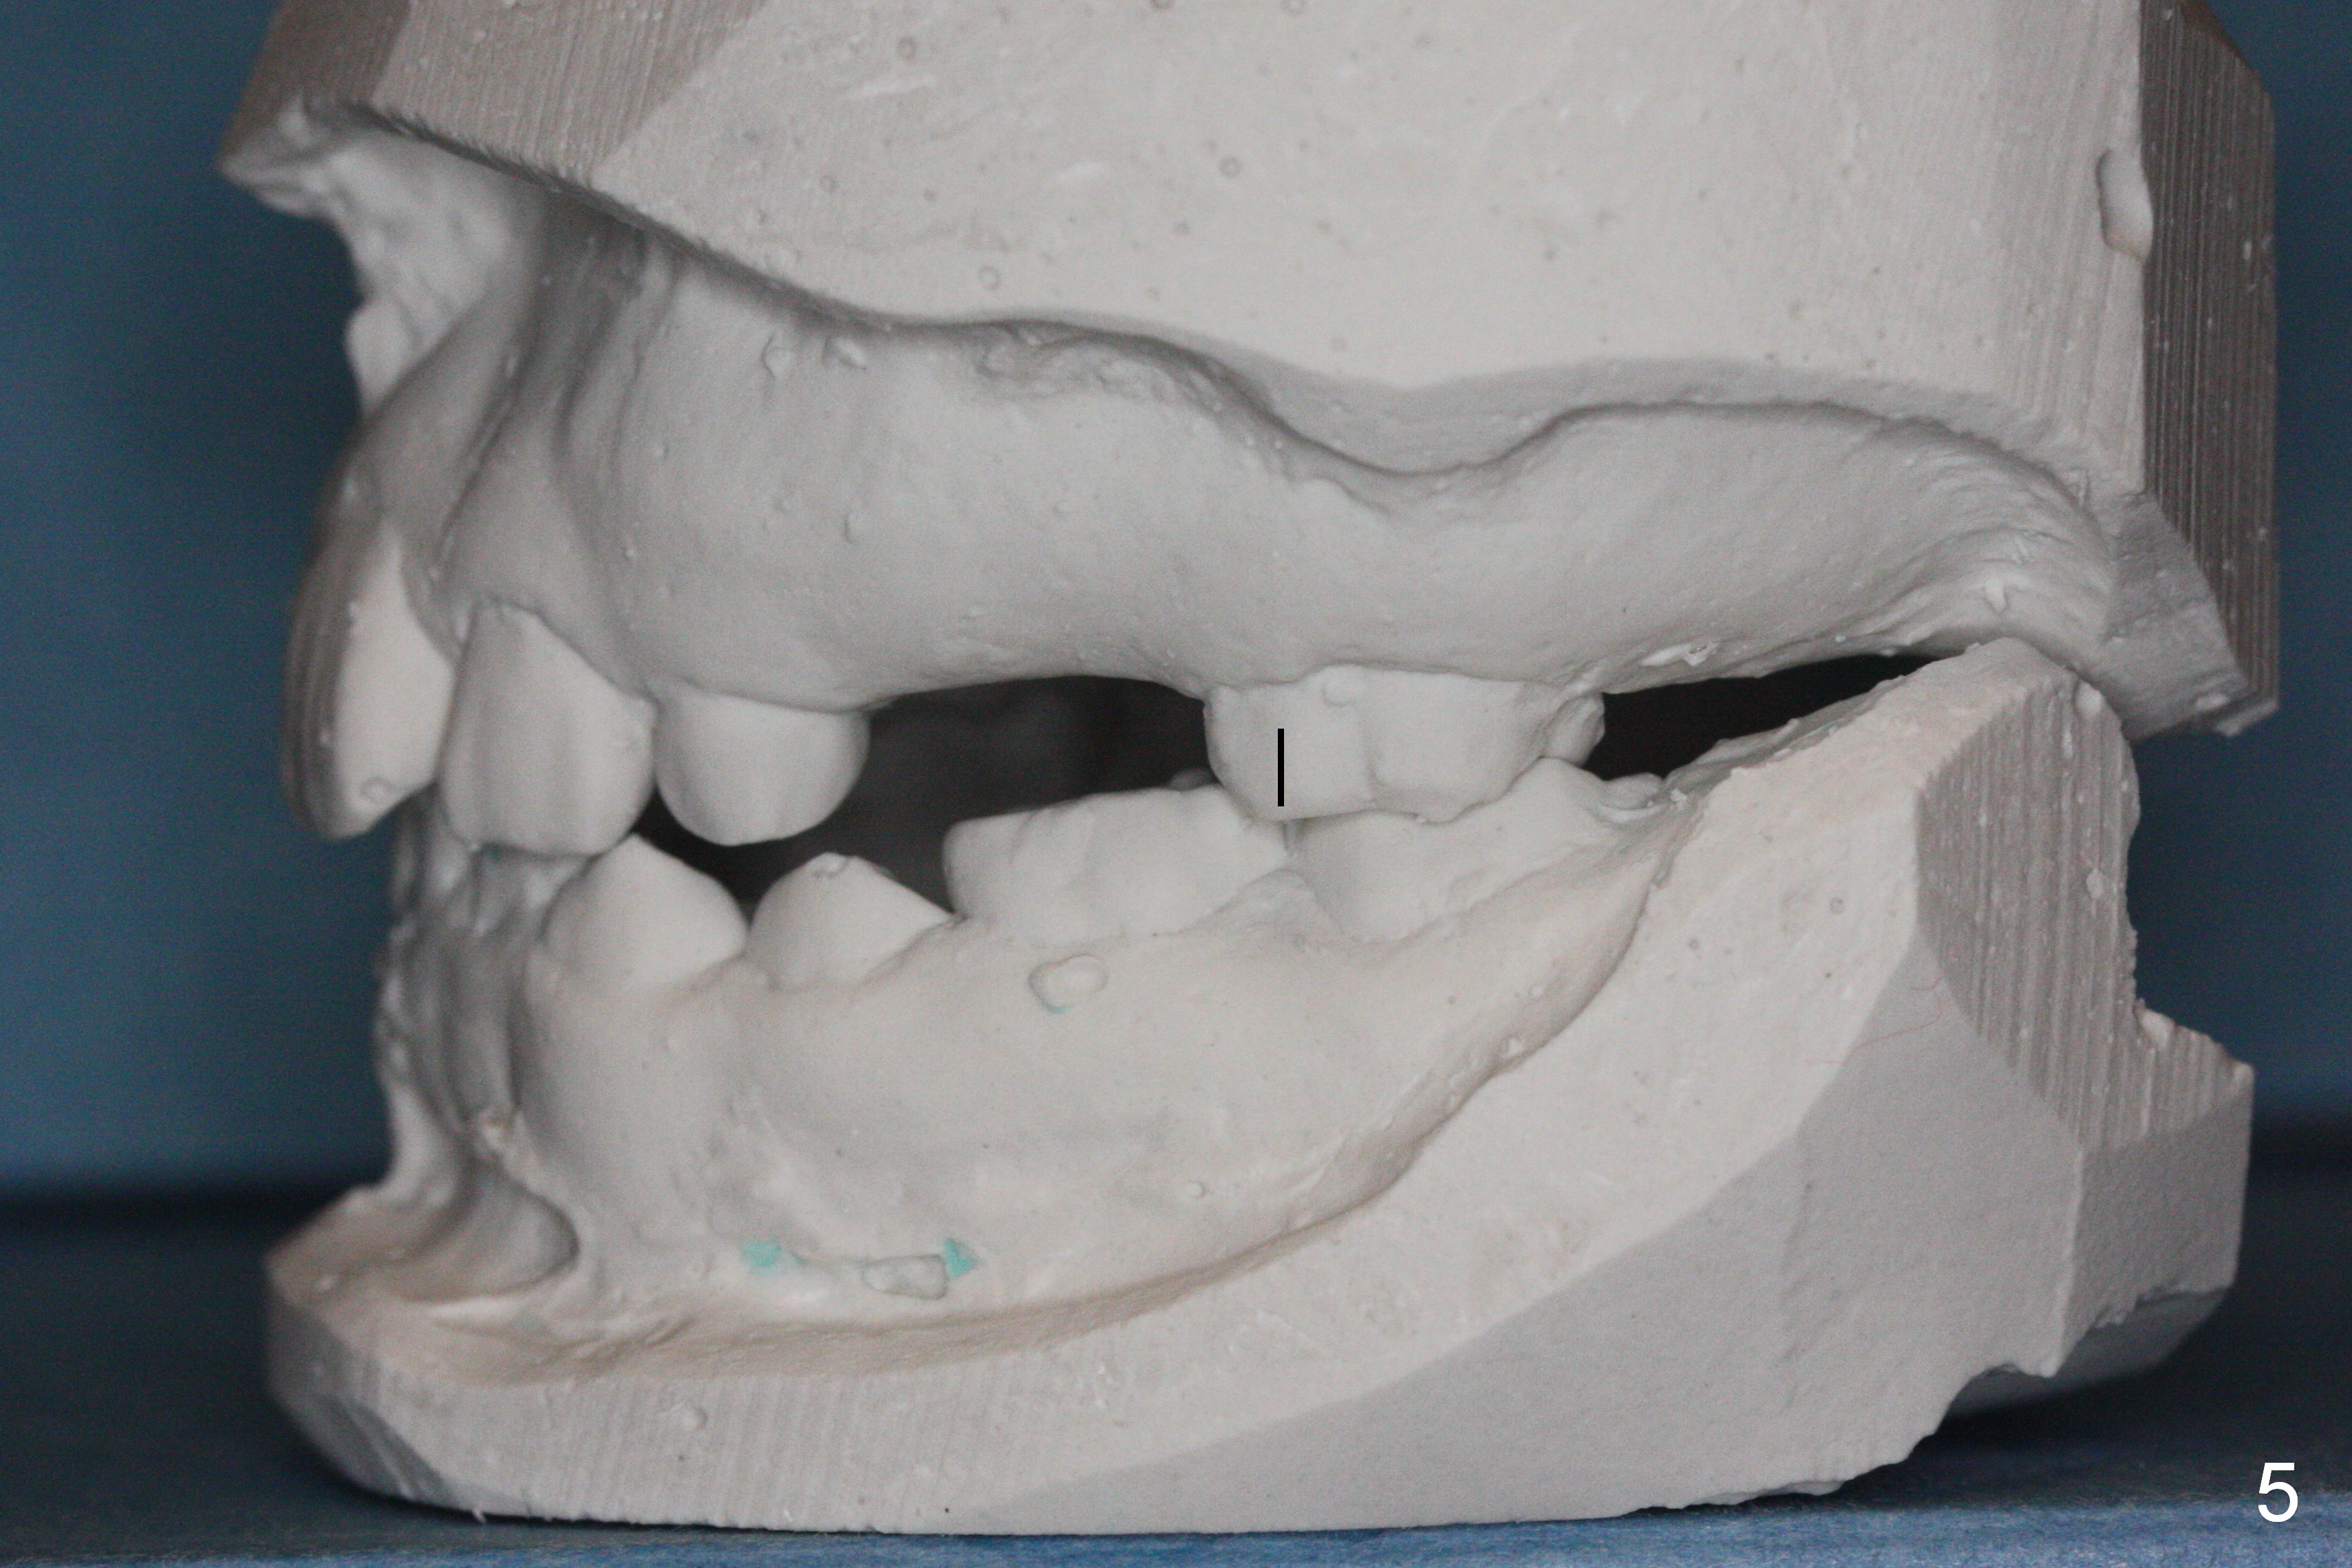

While the upper right bicuspids have erupted, the upper left ones are unerupted and blocked (Fig.2, 6). It appears that the tooth #14 has been mesially shifted (compare Fig.4,5). A space regainer is fabricated (Fig.9). It is not completely seated when cemented, especially at H. The wire holding open coil spring fractures next day. It appears that H is not a good anchor with mobility II. It should be extracted. The mesial anchor will be the tooth #10. If there is sign of anterior tooth protrusion after regainer activation, a mini implant (Tomas, Fig.10 red circle) should be placed in the anterior palate parasagitally and bonded to the cross palatal wire (^).

Nearly 2 months post regainer placement, UL6 appears to have been distalized (Fig.11 arrow), but UL4,5 have not erupted (Fig.12), while UL1,2 are displaced (Fig.13). Diode laser is used to expose the tooth buds, which are deeply seated (Fig.14). If they do not erupt soon, a mini implant should be placed for anchorage (Fig.10). Use several power chains to retract the anterior arm, while drill through the Nance appliance (high speed handpiece) for mini implant placement.